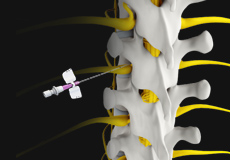

Epidural Spinal Injection

Epidural spinal injection is a non-surgical treatment option utilized for relieving back pain. Spine degenerative conditions such as herniated disc, spinal stenosis and many others may induce back pain due to the compression of the associated spinal nerves. This pain or numbness may extend to the other parts of the body such as hips, buttocks, and legs. Doctors start with non-surgical methods to treat back pain and epidural spinal injection is one of these preferences. In cases where the patient finds no relief from non-surgical methods then finally surgery is recommended.

Epidural Steroid Injections

Epidural steroid injection (ESI) is a minimally invasive approach to treat inflammation of spinal nerves that causes pain in the neck, arms, back and legs. This technique may help relieve back pain in conditions such as spinal stenosis, spondylolysis or herniated discs. In this technique, the steroidal medications are injected into the spinal canal so as to pass down to the inflamed spinal nerve through the epidural space which lies between the covering of the spinal cord and the vertebrae. An ESI contains a corticosteroid medication along with an anesthetic agent which can reduce the inflammation and pain.

Transforaminal Epidural Steroid Injection

The epidural space of the spine is the area between the vertebral bones and the protective dura sac that surrounds the spinal cord and nerves.

Spine Injections

Spine injection is a non-surgical treatment modality recommended for the treatment of chronic back pain. Injection of certain medicinal agents relieves the pain by blocking the nerve signals between specific areas of the body and the brain. The treatment approach involves injections of local anesthetics, steroids, or narcotics into the affected soft tissues, joints, or nerve roots. It may also involve complex nerve blocks and spinal cord stimulation.